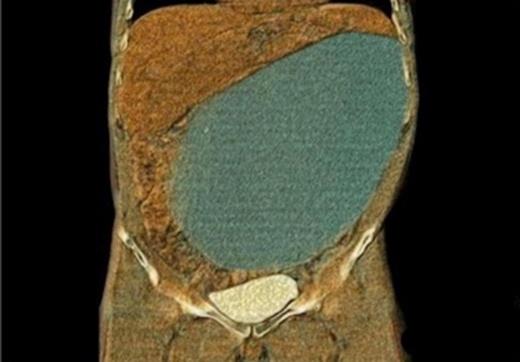

A 34-year-old patient was scheduled for minimal invasive mitral valve reconstruction to treat a Barlow syndrome with a prolapse of the posterior mitral leaflet. The patient’s medication consisted of a Proton pump inhibitor due to a chronic gastro-esophagial reflux disease. Otherwise the patient had no other digestive symptoms, in particular there was no history of pancreatic disease. Preoperative computed tomography (CT) incidentally showed a huge abdominal cystic lesion of 34x17x25cm (Fig. 1).

Different imaging modalities have been used to diagnose cystic intra-abdominal tumours. Some studies demonstrated ultrasonography as being superior compared with CT regarding the assessment of intracystic structures such as the presence of echogenic contents, a thickness of capsule, and intracystic septation, which may indicate internal bleeding or infection. In cystic lymphangioma, the fluid content is usually described as serous with a density similar to water (Houndfield unit (HU) = 0). Differential diagnosis of intraperitoneal cystic masses includes pancreatic pseudocysts, echinococcal cyst, enteric duplication cysts, cystic mesotheliomas and ascites. Abdominal CT in our patient revealed a density of 18 HU. Ecchinococcus serology was negative as well as the bacteriological and cytological analysis of the aspirated fluid.